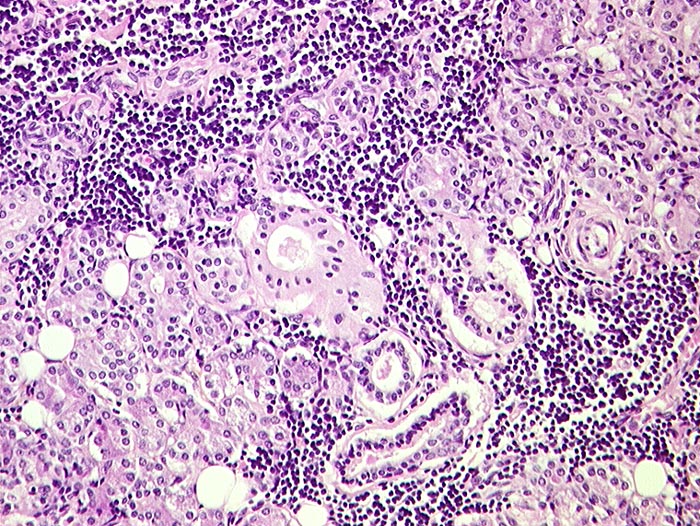

PathoPic ID 118 - Sjögren Syndrom, Parotis

Sjögren Syndrom, Parotis

Entzündung / Reparatur

Parotis

Kopf & Hals, Sinnesorgane

Chronische lymphozytäre Entzündung und Atrophie der Glandula parotis.

Sjögren Syndrom: St.n. Enukleation des linken Auges wegen spontaner Ruptur. St.n. Hornhautulzera.

Histologie